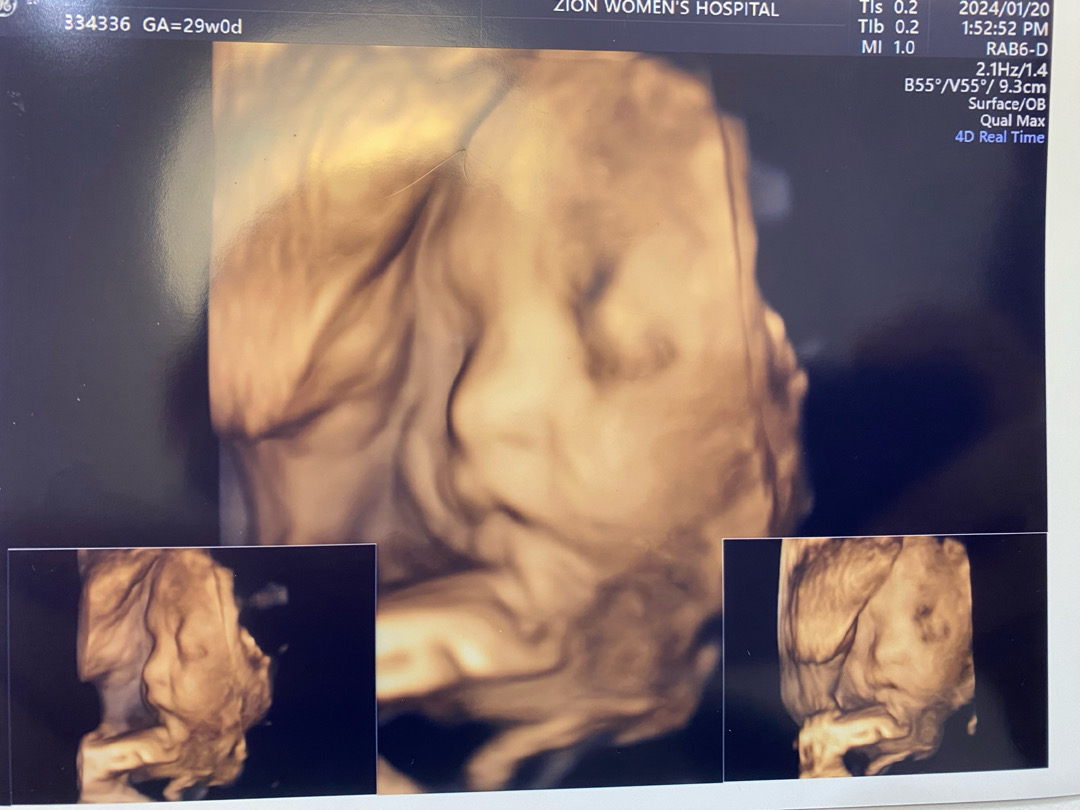

29주 입체초음파 👧🏻

29주 입체초음파 찍고왔는데 이대로 거의 얼굴 나온다고하더라구요.. 제 눈에 벌써 이쁜데 다른분들이봐도 콧대랑 이쁜얼굴상 아닌가요..?🤫